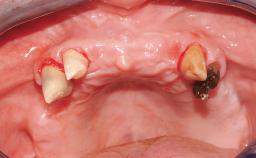

Surgical SAC classification

| SAC Level | - |

|---|---|

| Defining Characteristics | - |

| Modality | - |

| Placement Protocol | - |

| Tooth Site | - |

| Socket Morphology | - |

| Socket Integrity | - |

| Bone Volume | - |

| Anatomic Risk | - |

| Esthetic Risk | - |

| Complexity | |

| Risk of Complications | - |